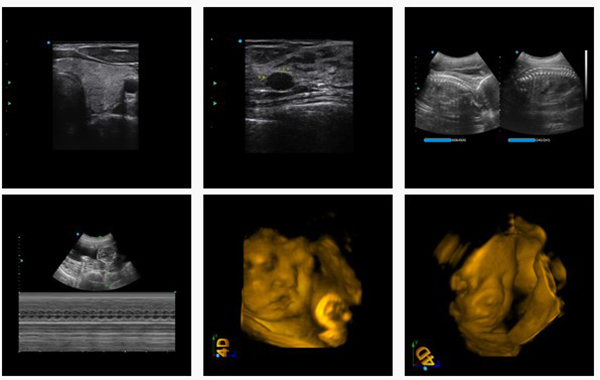

Siêu âm là một phương thức được sử dụng phổ biến đối với những mẹ bầu đang mang thai. Siêu âm gồm nhiều loại như siêu âm 2D, 3D, 4D trong đó thì siêu âm 2D được xem là loại siêu âm đen trắng. Với hình thức siêu âm này cũng giúp các bác sĩ có thể theo dõi được sự phát triển của thai nhi cùng những bất thường xảy ra trên cơ thể bé.

– Siêu âm màu 3D hay 4D các mẹ cần phải hạn chế ở mức tối đa vì chúng ảnh hưởng tới sự phát triển của bé.